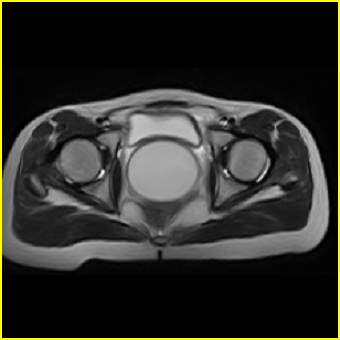

女、15岁、下腹疼痛2天,排尿困难1天。查体:处女膜闭锁,距处女膜约4至5cm处扪及一约5cm直径的圆形包块,张力较高,触痛明显、欠活动。b超提示子宫增大伴宫内增强回声团。

影像意见:子宫直肠陷凹积血。

更正影像意见:阴道积血。

处女膜闭锁,阴道积血

处女膜闭锁,阴道积血,子宫积血.

阴道积血,子宫积血.

子宫及阴道积血。

处女膜闭锁,伴子宫及阴道积血.